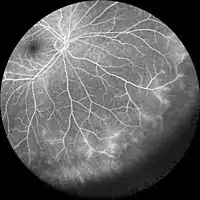

Optical coherence tomography angiography (OCTA) and Fluorescein angiography to visualize the vascular networks of the retina and choroid.